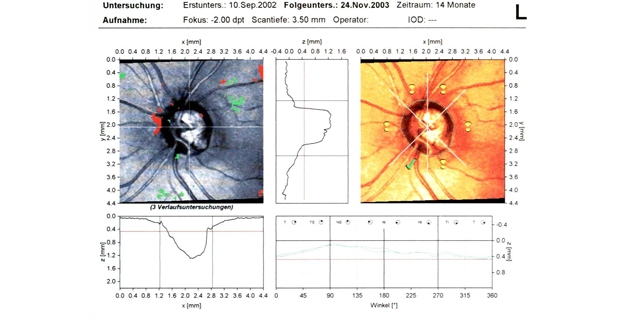

Da die Dicke der Hornhaut Einfluss auf die Augeninnendruckwerte hat, erfolgt zunehmend die Hornhautdickenmessung (Pachymetrie) zur kritischen Überprüfung der Werte. Hohen differenzialdiagnostischen Stellenwert haben auch die Beurteilung des Kammerwinkels (Gonioskopie) und des Sehnervenkopfes. Mittels optischer Cohärenztomographie (OCT) ist eine Quantifizierung des Verlustes an neuroretinalem Gewebe möglich. Die fotografische Dokumentation von Papille und Nervenfaserschicht erleichtert die Verlaufsbeurteilung. Die Gesichtsfelduntersuchung (Perimetrie) ist ein entscheidender Teil der Diagnostik.